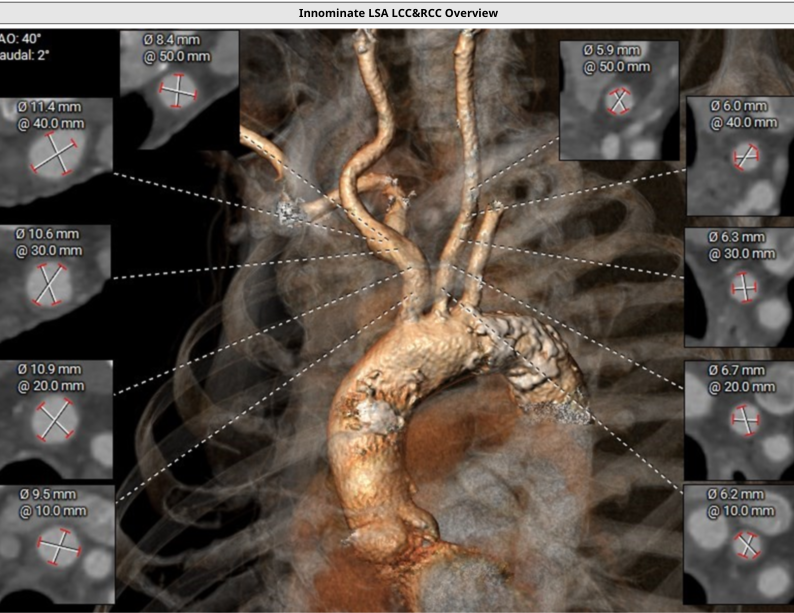

弓上血管

弓上血管无明显迂曲钙化,脑保护入路条件良好

Procedure process—弓部血管造影